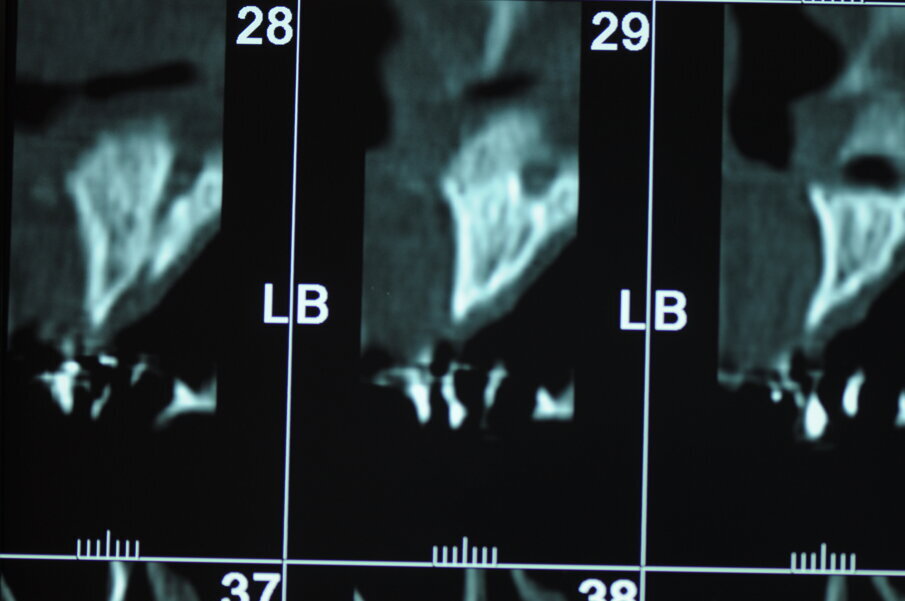

Figg. 3, 4 - Valutazione dei volumi ossei all'esame TC.